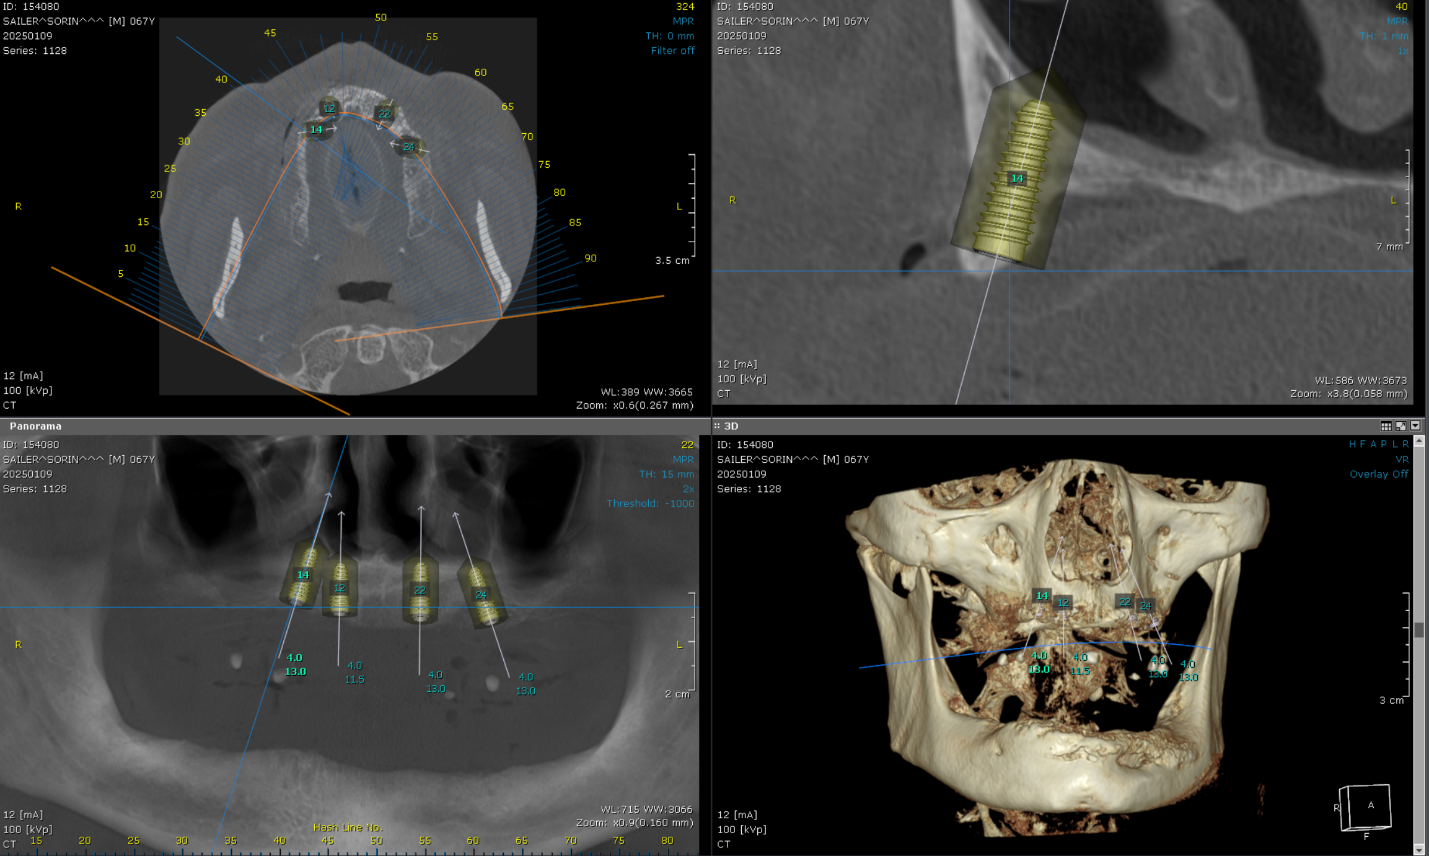

Cone Beam Computed Tomography (CBCT) scans were acquired for both the maxillary and mandibular arches. These scans provided critical insights into available bone volume, bone density, and anatomical considerations, forming a foundation for precise implant planning and guided surgery.

Bone was measured to asses the amount of bone gained and the density of the said bone and also a first simulation of implant placement was performed.

Implant placement planning done in EXOPLAN involved careful digital matching of the CBCT, wax-up, and facial scan data, resulting in an accurate, digitally-produced try-in prosthesis (Fig. 8). The validated prosthetic design was subsequently integrated with the software to plan placement of five strategically positioned implants in the upper arch.